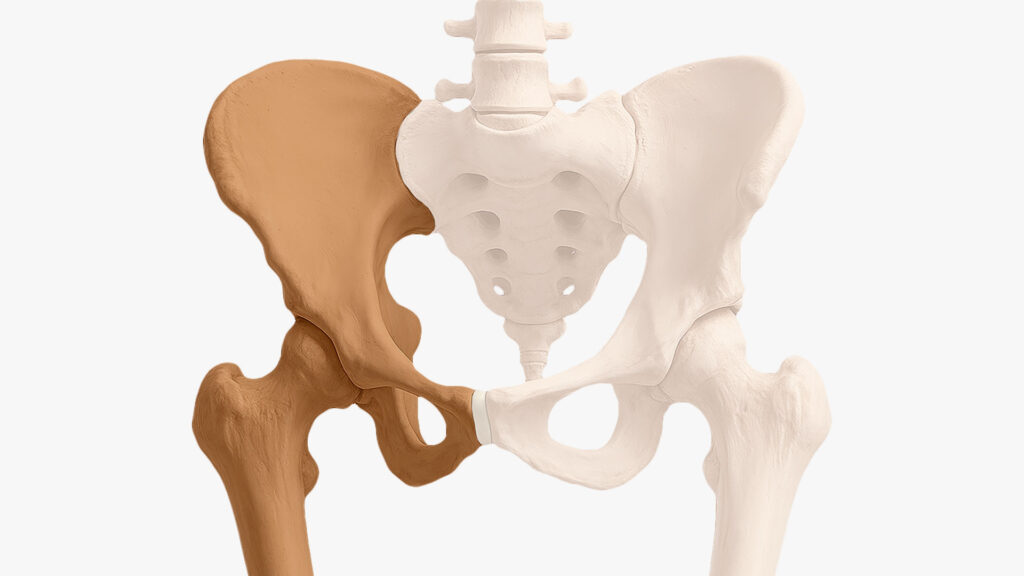

Pelvis

Es el conjunto de huesos que une el tronco con las piernas. Está formada por los huesos ilíacos (derecho e izquierdo), el sacro y el cóccix. La pelvis es toda la estructura ósea.

Cadera

Es la unión entre el fémur (hueso del muslo) y el acetábulo (cavidad de la pelvis). Es una articulación esférica que permite mover la pierna hacia adelante, atrás y hacia los lados.

Acetábulo

Es una cavidad en la pelvis, con forma de media esfera, donde encaja la cabeza del fémur.

- Funciona como el receptáculo que sostiene la cabeza femoral.

- Distribuye las cargas para evitar desgaste rápido.

- Está recubierto de cartílago para que el movimiento sea suave y sin fricción.